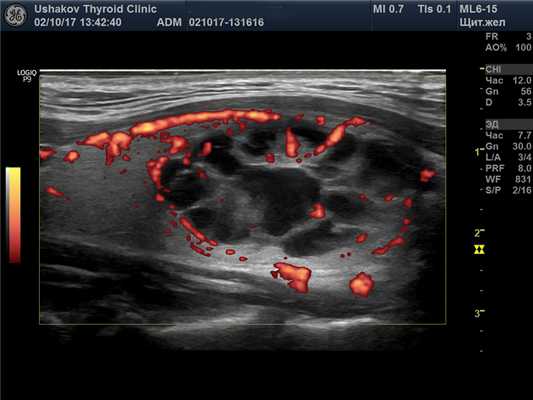

(Справа) Энергетическая допплерография, поперечная проекция: определяется диффузное повышение васкуляризации железы, часто описываемое как «тиреоидный пожар» при болезни Грейвса. При спектральной допплерографии (изображения не показаны) в сосудах обнаруживается повышение скорости кровотока в отличие от тиреоидита Хашимото (скорость не изменена). (Слева) КТ глазниц, корональная реформатированная проекция: определяется распространенная гипертрофия экстраокулярных мышц, сопоставимая с офтальмопатией Грейвса.

(Справа) Энергетическая допплерография, продольная проекция: определяется «тиреоидный пожар». При выраженной васкуляризации железы для оценки кровотока и уменьшения выраженности артефактов можно использовать высокую частоту повторения импульсов и фильтры.

о Цветовая допплерография: выраженная диффузная гиперваскуляризация паренхимы, «тиреоидный пожар»

о Спектральная допплерография: повышение пиковой скорости кровотока (до 120 см/с) в нижней щитовидной артерии